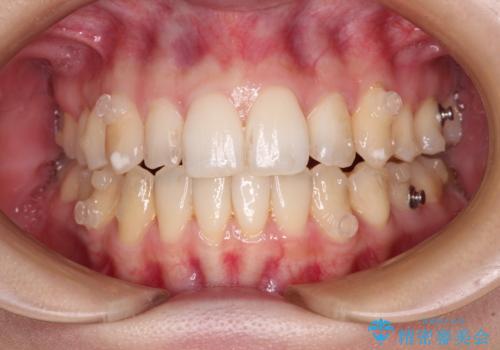

補助装置を併用したインビザラインでの八重歯の抜歯矯正

- 八重歯と奥歯の咬み合わせを気にして来院された患者様です。

インビザラインによる矯正治療を希望されたため、八重歯改善のための抜歯矯正部分は補助装置を併用し、その後はインビザラインにて行うこととしました。

下顎の右側変位が顕著であったため、ワイヤー矯正の方が咬み合わせは改善しやすいのですが、ある程度は時間がかかっても良いとのことであったので、インビザラインにて矯正治療を行うこととしました。

骨格的に下顎が右側に変位していたため、上下正中を合わせることは困難であることは分かっていました。それでも、なるべく合わせるようにとしたため、治療期間は長期間となりました。

長期間とはなりましたが、咬み合わせが改善され、患者様には大変満足していただきました。